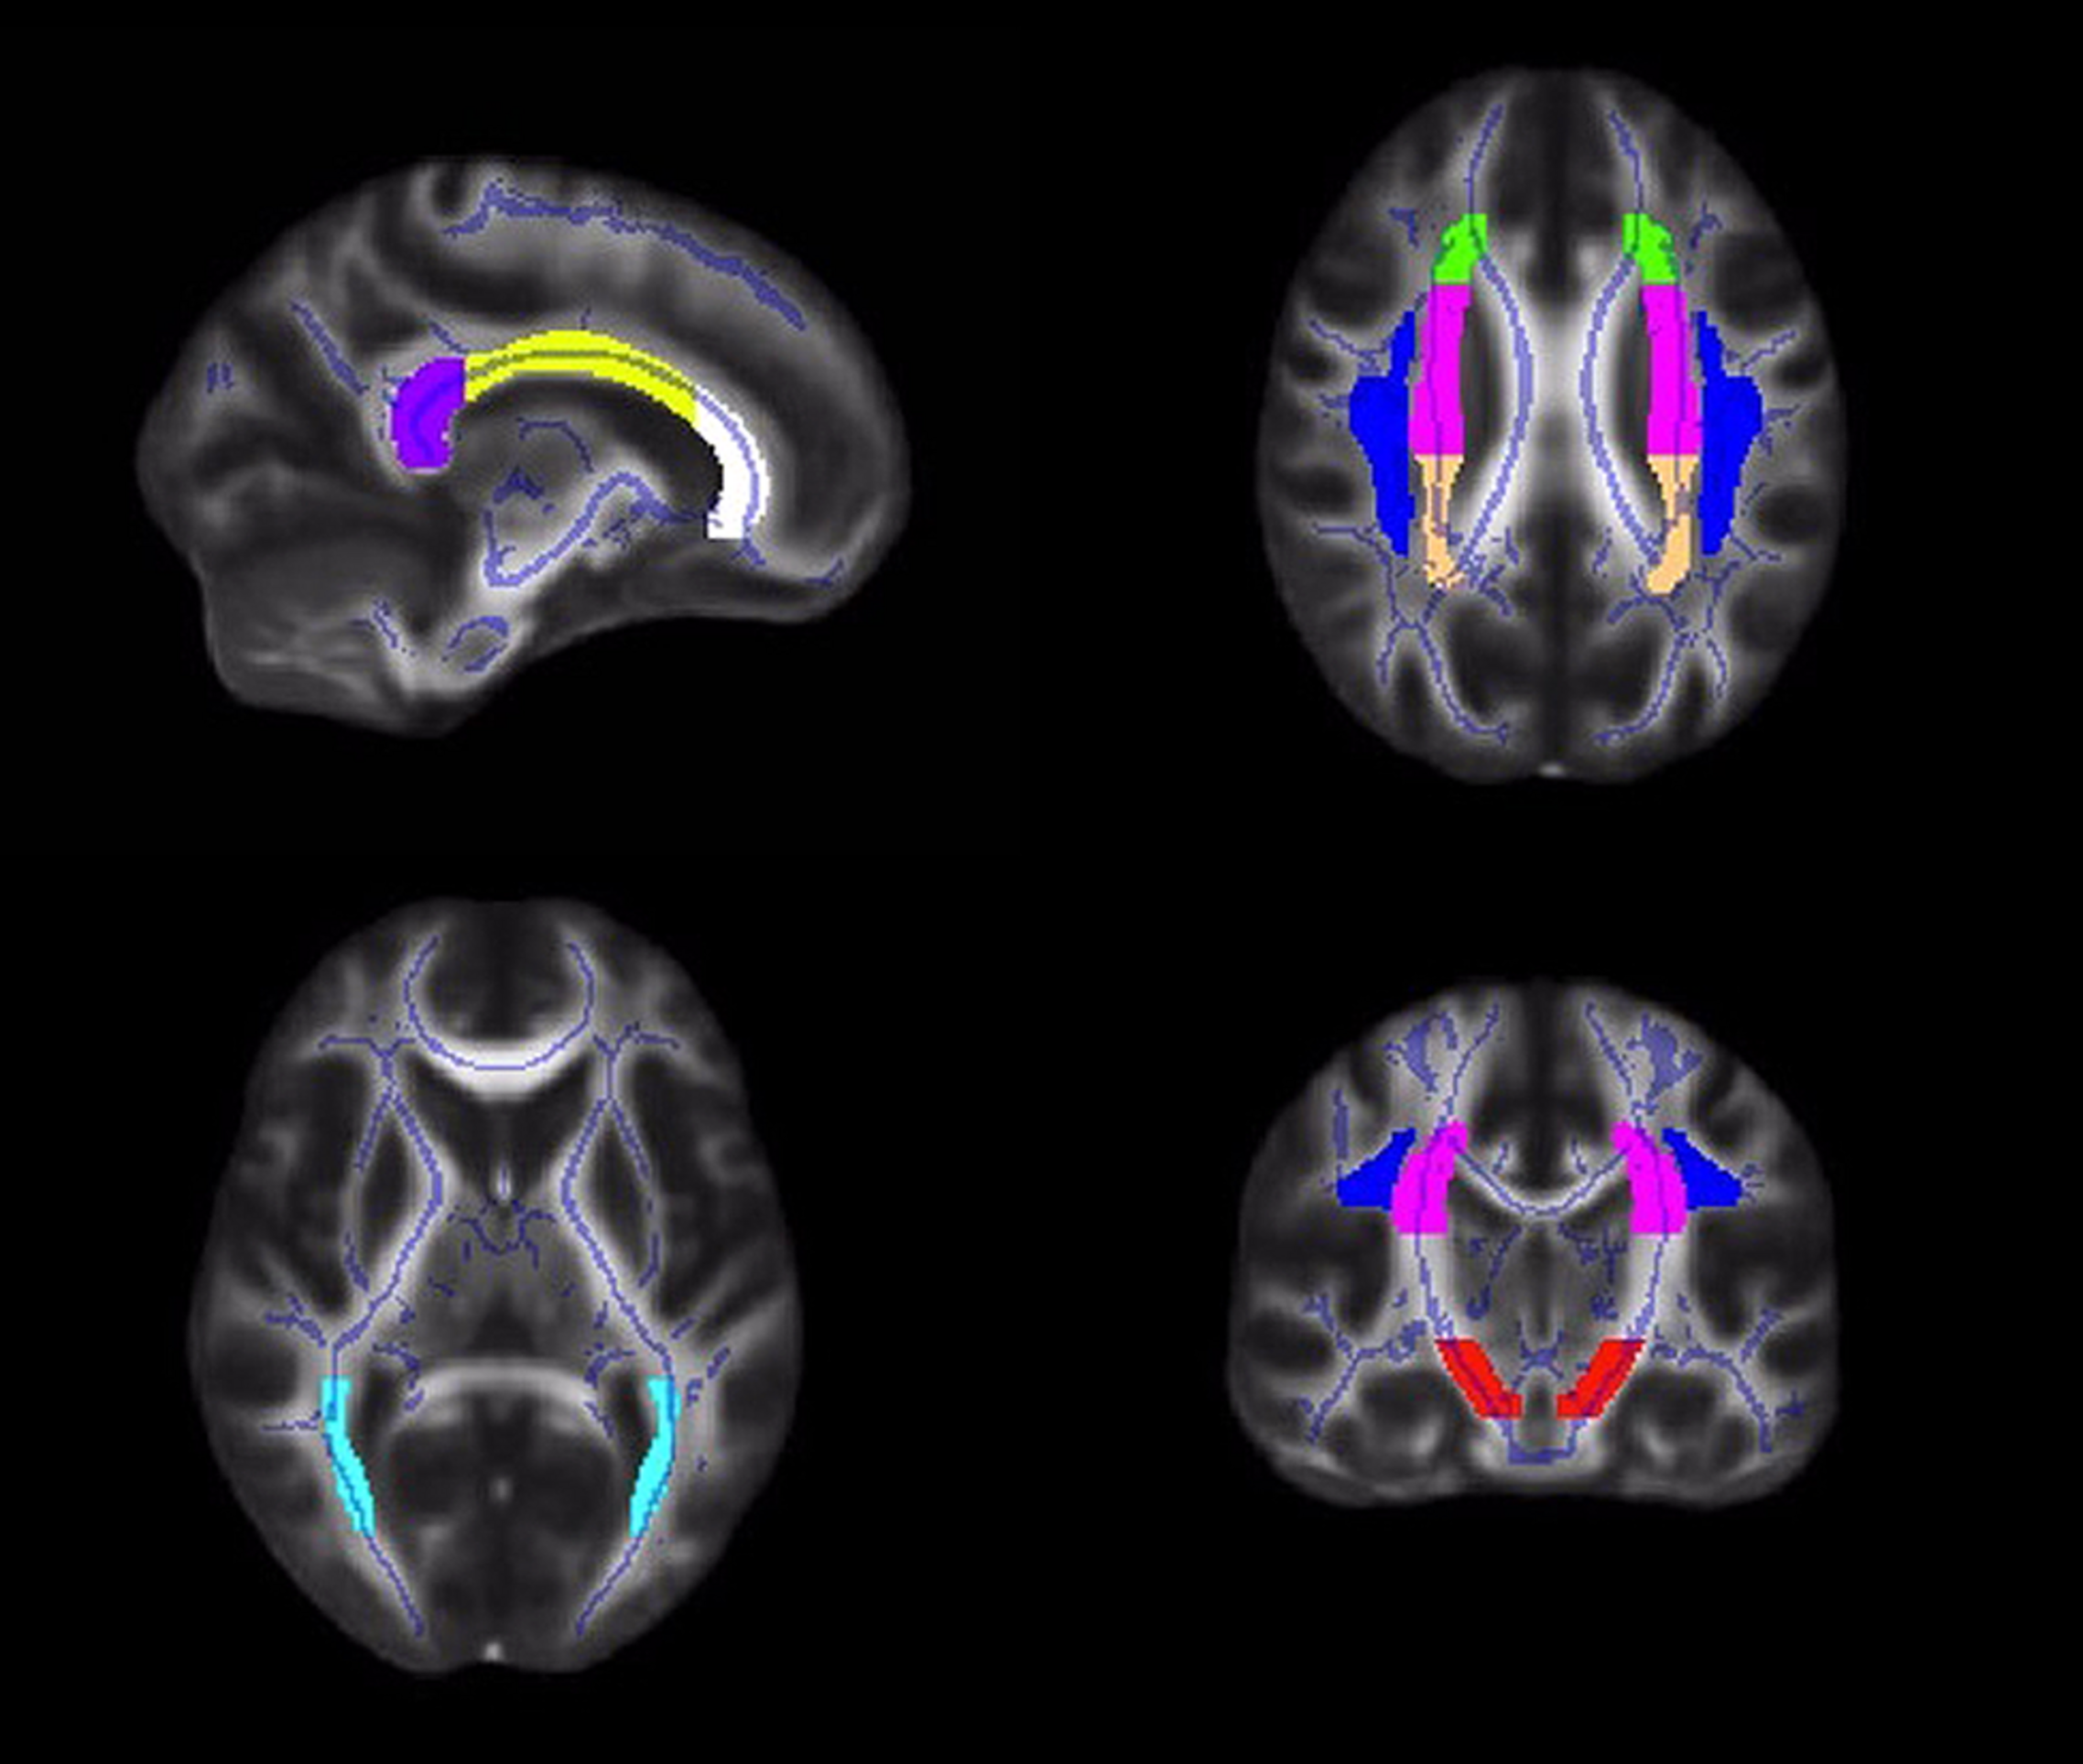

Diffusion values (FA, RD, AD) were calculated for each participant within a priori ROIs, created from the JHU ICBM-DTI-81 white matter labels atlas2 (Mori et al., 2005; Wakana et al., 2007; Hua et al., 2008). Tract ROIs were created in the genu, body and splenium of the corpus callosum, and the left and right corona radiata, superior longitudinal fasciculus, posterior thalamic radiation, and cerebral peduncle (Figure 1). An FSL command, fslmaths, was used to create each ROI (e.g., fslmaths JHUAtlas –uthr 16 –thr 16 RCerebralPeduncle).

FIGURE 1

Illustrations of the white matter tract ROIs in the corpus callosum (white = genu; yellow = body; purple = splenium), corona radiata (anterior = green; superior = pink; posterior = peach), superior longitudinal fasciculus (blue), posterior thalamic radiation (light blue), and cerebral peduncle (red).